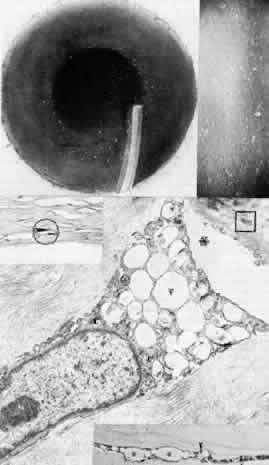

Fig. 4. Sclerocornea. Schematic drawing of ocular features Top left. In a minimally affected patient with additional findings of ptosis, strabismus, and hearing loss, only the peripheral cornea is opacified. Top center. In this advanced case with chromosomal translocation and multiple congenital abnormalities, the entire cornea is sclerified and the fine vascular arcades extend centrally from the conjunctiva and sclera. Top right. Light micrograph of anterior cornea shows edematous disorganization of epithelium, fragmentation of Bowman's membrane (B), and interstitial vascularization (V) (hematoxylin-eosin, × 200). Middle left. Transmission electron micrograph of normal human corneal stroma is shown for comparative purposes. Note uniform 240- to 260-nm collagen fibril diameter (× 50,000). Middle right. Transmission electron micrograph of sclerocornea at same magnification shows disorganized array of collagen fibrils that measure as much as three times normal diameter (× 50,000). Bottom. Transmission electron micrograph of posterior cornea shows abnormal Descemet's membrane of less than 1μm thickness (DM, bracketed) and attenuated endothelial cells (× 10,500). (Schematic. Grayson M: Diseases of the Cornea, p 32. St. Louis, CV Mosby, 1979; Top center and right. Rodrigues MM, Calhoun J, Weinreb S: Sclerocornea with an unbalanced translocation [17p, 10q]. Am J Ophthalmol 78:49, 1974)

Ultrastructural studies22,46,47 have shown the involved stroma to assume the morphologic features of scleral tissue, with irregularly arranged collagen fibrils of variable and immensely enlarged diameter for corneal tissue (up to 150 nm, comparable to normal scleral collagen). The precise lamellar organization of normal corneal stroma is not present; thus optical clarity is not achieved. Various abnormalities of endothelium and Descemet's membrane exist, from attenuation to focal absence. Descemet's membrane is generally thin, with multilaminar deposition of basement membrane-like collagen.

Pathophysiologically, sclerocornea may result from developmental arrest of limbal differentiation during neural crest migration, as occurs with the other mesenchymal dysgeneses.22